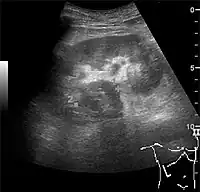

Figure 20. Staghorn calculi filling the entire collecting system and creating pronounced shadowing.[1]